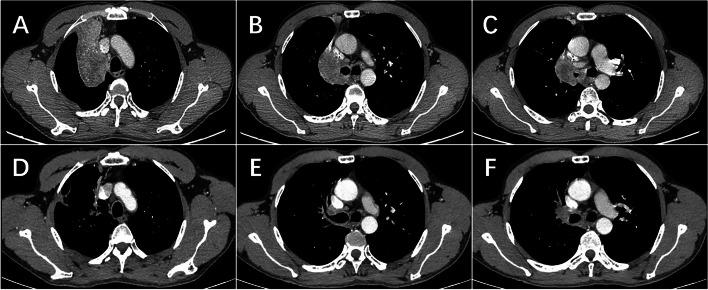

In recent years, neoadjuvant immunotherapy with chemotherapy has shown increasing promise for locally advanced non-small cell lung cancer (NSCLC). However, to establish its clinical efficacy and safety, it is imperative to amass more real-world clinical data. This retrospective study aims to assess the safety and effectiveness of combing sintilimab, a PD-1 inhibitor, with chemotherapy as a neoadjuvant treatment modality in patients diagnosed with potentially resectable NSCLC.

We retrospectively reviewed patients with stage II-III NSCLC receiving neoadjuvant chemoimmunotherapy in Sichuan Cancer Hospital between February 2021 and February 2023. Sintilimab injection (intravenously,200 mg, iv, d1, q3w) and platinum-based chemotherapy were administered intravenously every 3 weeks, with radical lung cancer resection planned approximately 4-11 weeks after the last dose. The primary endpoint of the study was pathologic complete response (pCR). The secondary endpoints were objective response rate (ORR), and safety.

Thirteen patients were enrolled, they were mostly diagnosed with stage III NSCLC (IIB 15.4% IIIA 38.5%; IIIB 46.2%). Most of them had pathologically confirmed squamous cell carcinoma (69.2%). All patients received sintilimab combined with platinum-based chemotherapy for 2 to 4 cycles. Notably, none of the patients necessitated a reduction in initial dosages or treatment postponement due to intolerable adverse events. Then, all of them underwent surgical operation. Impressively, nine patients (69.2%) achieved a pathologic complete response. The objective response rate (ORR) stood at 46.15%. Nine patients experienced neoadjuvant treatment-related adverse events (TRAEs), with only one patient (7.6%) encountering a grade 4 neoadjuvant TRAE.